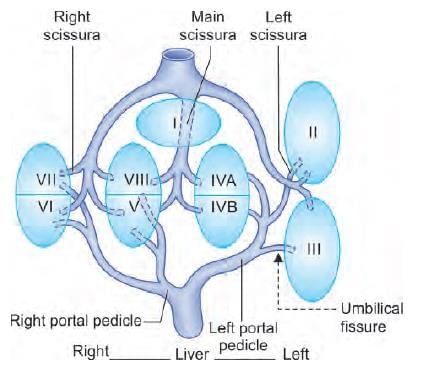

Liver is divided into eight segments according to Couinaud’s classification based upon. (AIIMS May 2019)

In CT scan of liver, identify the arrow marked segment: (INI-CET Nov 2022)